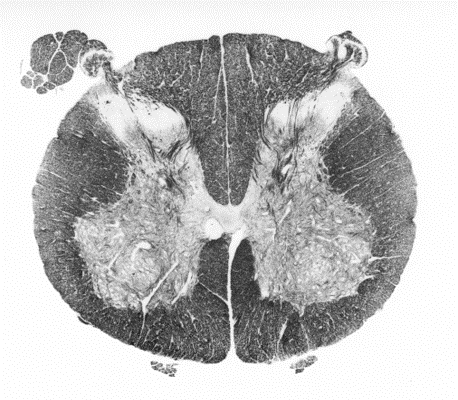

thoracic region of the spinal cord